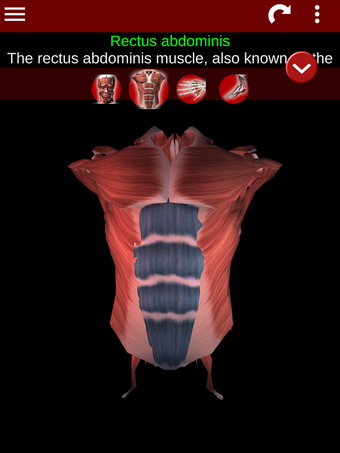

Esta herramienta educativa proporciona una descripción de cada músculo del cuerpo humano, así como un modelo tridimensional del sistema muscular. Con sólo tocar con el dedo, la aplicación revelará la información pertinente.

Los usuarios pueden hacer zoom sobre el músculo, así como elegir si ocultar o mostrar los datos. La orientación puede ser horizontal o vertical, según convenga más.